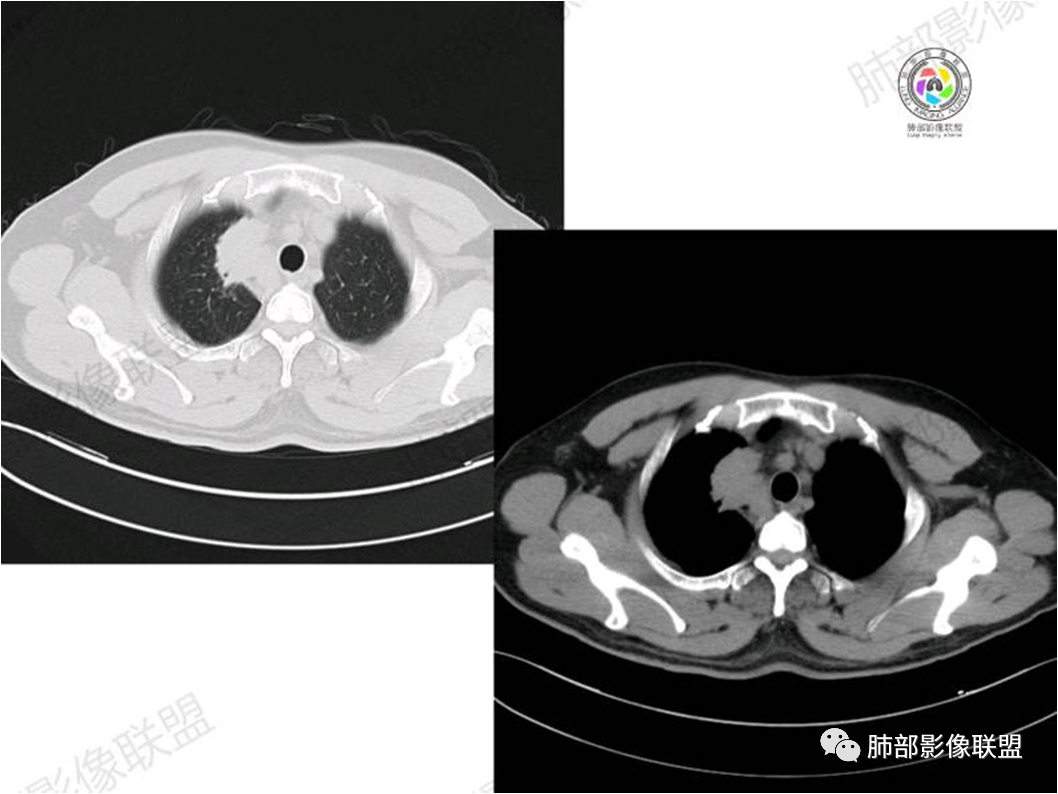

胸部CT:

MALT淋巴瘤影像表现为实变、结节及磨玻璃影,其中实变是其特点,胸膜下或支气管血管束节段性分布具有特征性,跨叶征较常见,这可能与肿瘤细胞进入血循环后往往又回到上皮黏膜部位,它们从一处黏膜到另一处黏膜,但不会到外周淋巴组织等有关。国外多名学者的影像-病理研究报道认为其病理学基础是由于肿瘤细胞沿支气管血管束周围间质及胸膜浸润生长,形成小叶间隔增厚、支气管血管束增粗等间质性改变,进一步浸润肺泡壁、充填肺泡腔。

①实变的出现率100%,多表现为两(89%)或单肺多发,密度均匀,与邻近胸壁肌肉的密度大致相等,少见钙化(15%),这与病灶内血管保持 完整,血供丰富,且肿瘤生长缓慢,对缺氧耐受好,不易坏死有关。边缘磨玻璃影或晕征具有特异性,其病理学基础是肿瘤细胞对小叶间隔、肺泡壁的淋巴瘤样浸润;

③扩张的充气支气管为其较特征性的表现,出现率约为89%,支气管管壁无破坏,支气管常扩张并达病灶的边缘,这与炎症性肺癌明显不同,其病理学基础是肿瘤起源于肺间质,肿瘤细胞沿着脏器解剖结构生长,周围增生的结缔组织牵拉导致支气管扩张,因而这类支气管扩张在肿瘤治疗后有时可消失;

④血管造影征是另一 点,强化的肺血管形态及走行正常,无扭曲或增 粗,其病理学基础为肿瘤细胞沿间质增生浸润,不破坏血管或支气管,病灶内肺支架结构完整,本研究发现率为75%;